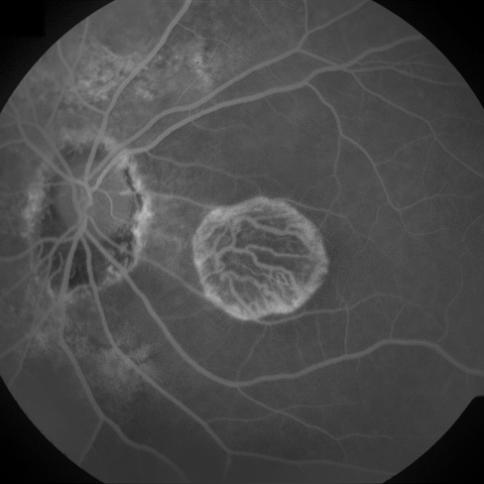

Figure 7: Three FA fundus images with symptom of GA and corresponding generated images. (a), (b), (c) Original images. (d), (e), (f) Generated images.

4.4 DCGANs and WGANs

In this section, DCGANs and WGANs are trained with thousands of CFP and FA images that have symptoms of drusen and GA separately; both of the models require four to six hours to train. Generated images have been diagnosed by ophthalmologists for verification. Images generated by DCGANs, which are shown in Fig. 8, cannot be identified as a valid retinal image with symptom. However, drusen and GA images generated by WGANs can be used by ophthalmologists to diagnose. In Fig. 9, generated drusen images are diagnosed as insignificant of drusen but can be identified by EyeNet. As for generated GA images in Fig. 9, irregularly shaped macular atrophy can be identified by an ophthalmologist. Macular atrophy is a distinguishable trait of GA, which means WGANs indeed learn the symptoms of drusen and GA from specific AMD and generate new images. Thus, WGANs perform better than DCGANs because of resolution. Structure of DCGANs limits the size of generated images to be 64x64, so some pathological details are lost. We choose WGANs for following experiments.